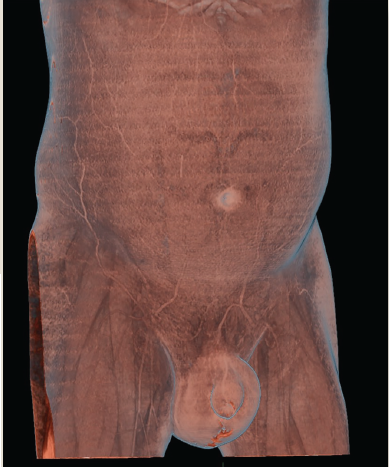

Paciente del sexo masculino, de 45 años que ingresó al servicio de urgencias tras haber iniciado su padecimiento hacía 48 horas. Refirió dolor testicular 7/10 en la escala de escala visual analógica (EVA), con aumento de volumen gradual, así como lesión ulcerativa en el rafe (figura 1); 24 horas antes de su ingreso refirió exudado purulento a través de la lesión ulcerativa con posterior salida de materia fecal.

Imagen: Pérez Ladrón de Guevara et al.

Figura 1 Reconstrucción tridimensional en donde se observa el aumento de volumen escorial y lesión ulcerativa en el rafe